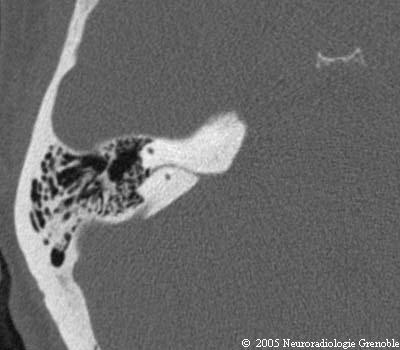

Radioanatomie TDM du rocher normal

Canal semi circulaire supérieur

Canal pétro-mastoïdien

Cellules mastoïdiennes